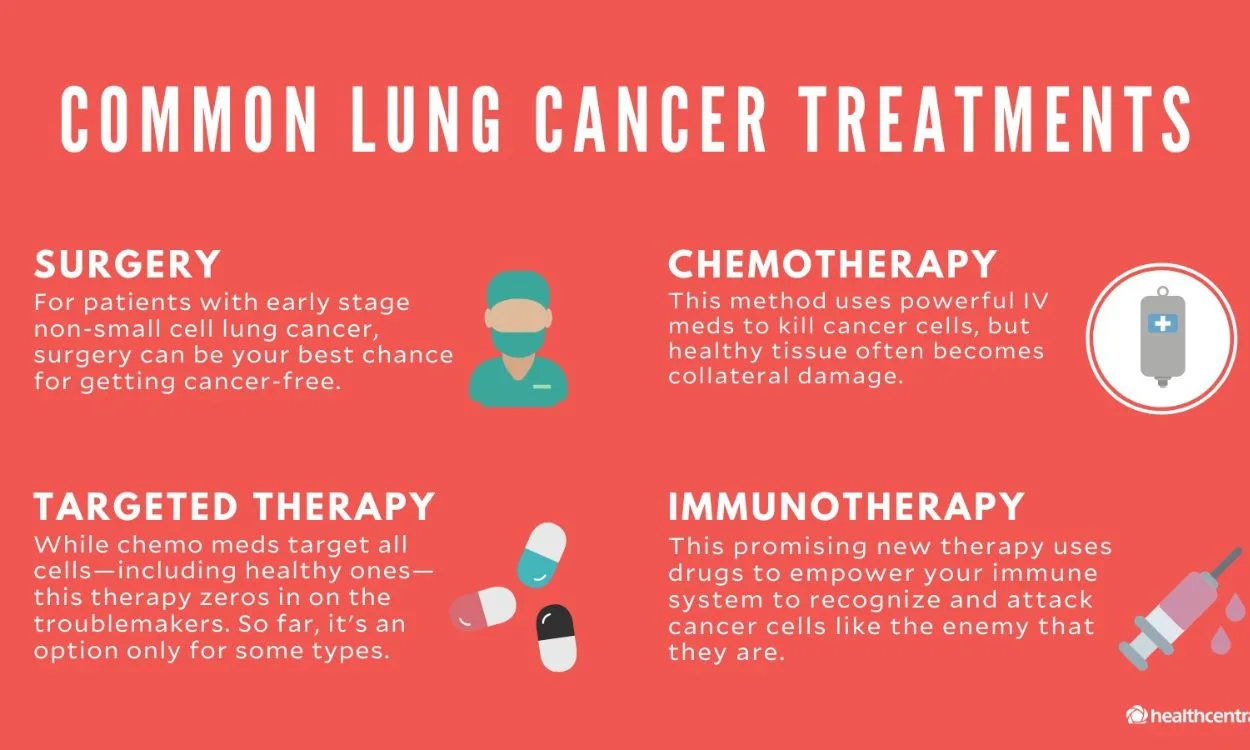

- Lung disease(52)

- Lung Health(52)